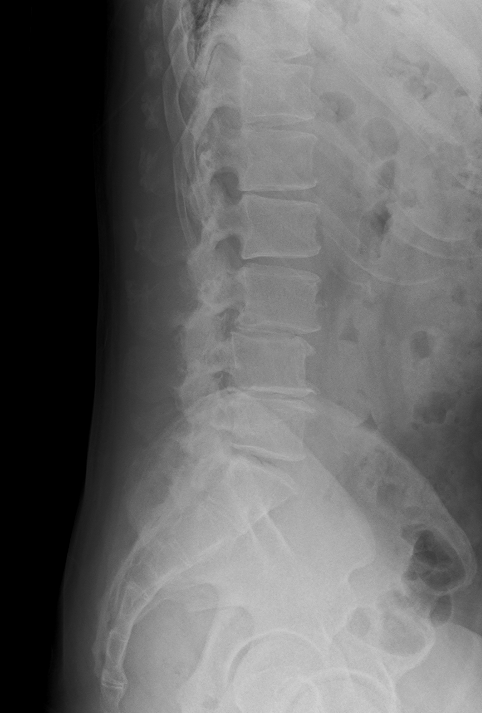

腰椎すべり症/ 脊柱管狭窄症

主訴 腰痛 左下肢痺れ

視診 左椎間板症状様疼痛回避姿勢

整形外科テスト SLRテスト 20°左(+++)

筋力検査 左長母趾伸筋低下

その他 輻輳反射 左低下